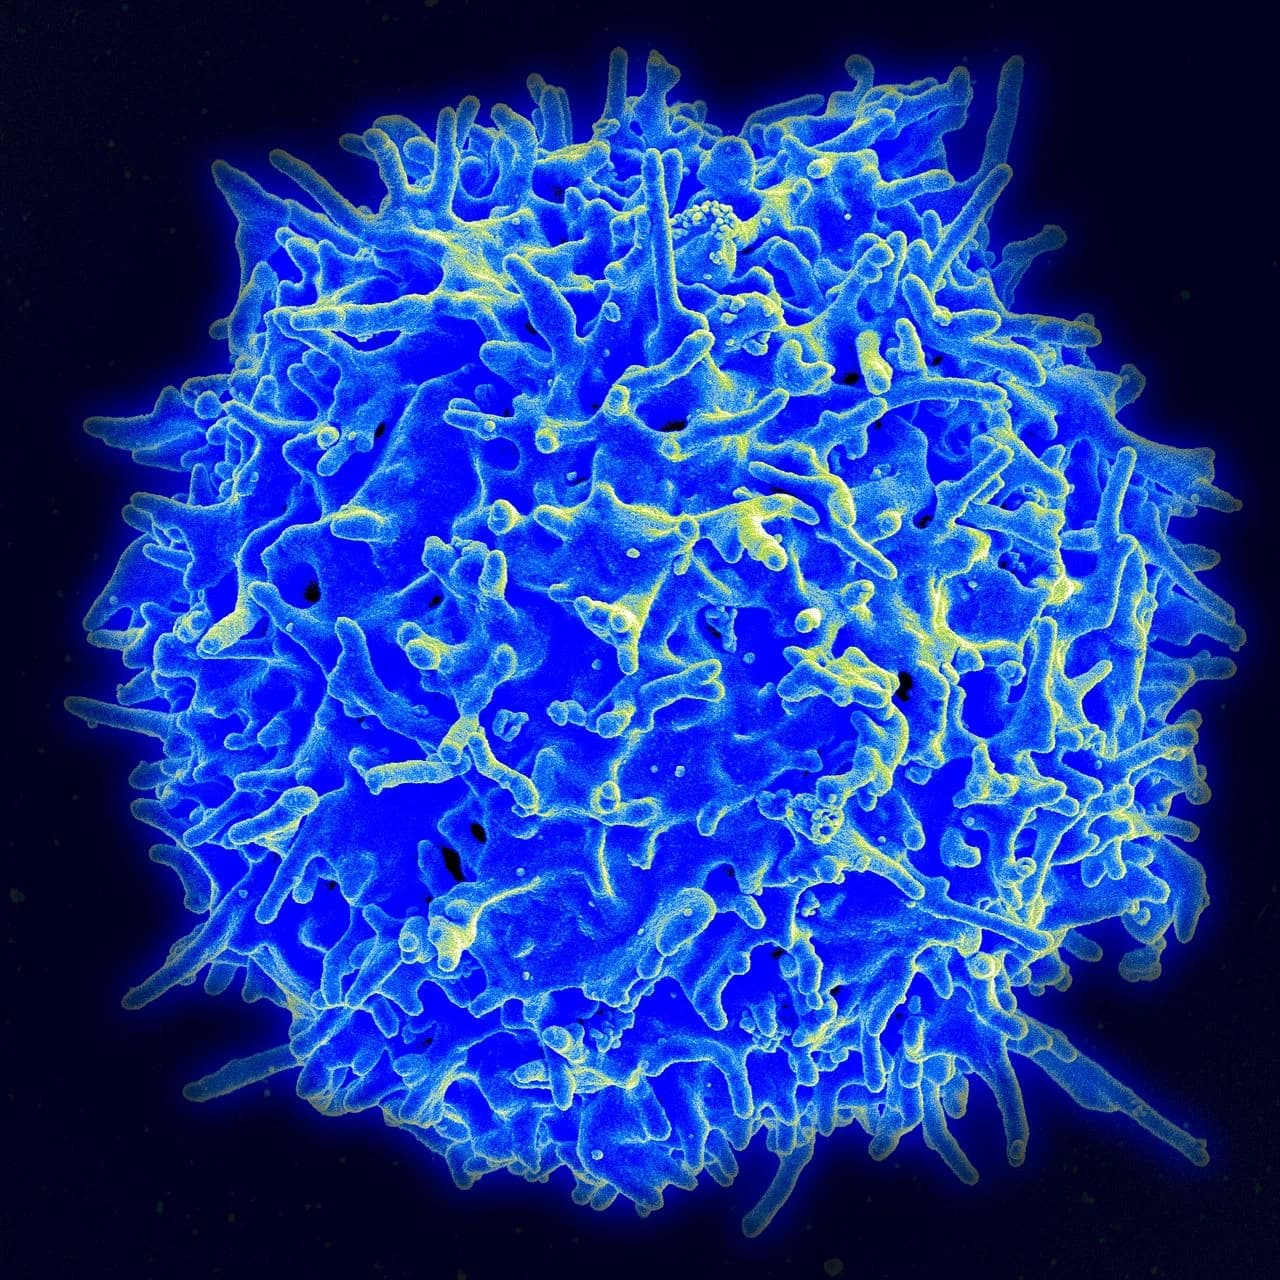

Melatonin is a hormone produced by the pineal gland used by every cell in the body.

- Helps the immune system R

10. Regulates Immune System

Melatonin improves states of immunity. R

It enhances TH2. R

Melatonin encouraged the proliferation of Th cells and improved their ability to secrete IL-4, but down-regulated the levels of IL-2 and IFN-gamma (interferon-gamma). R